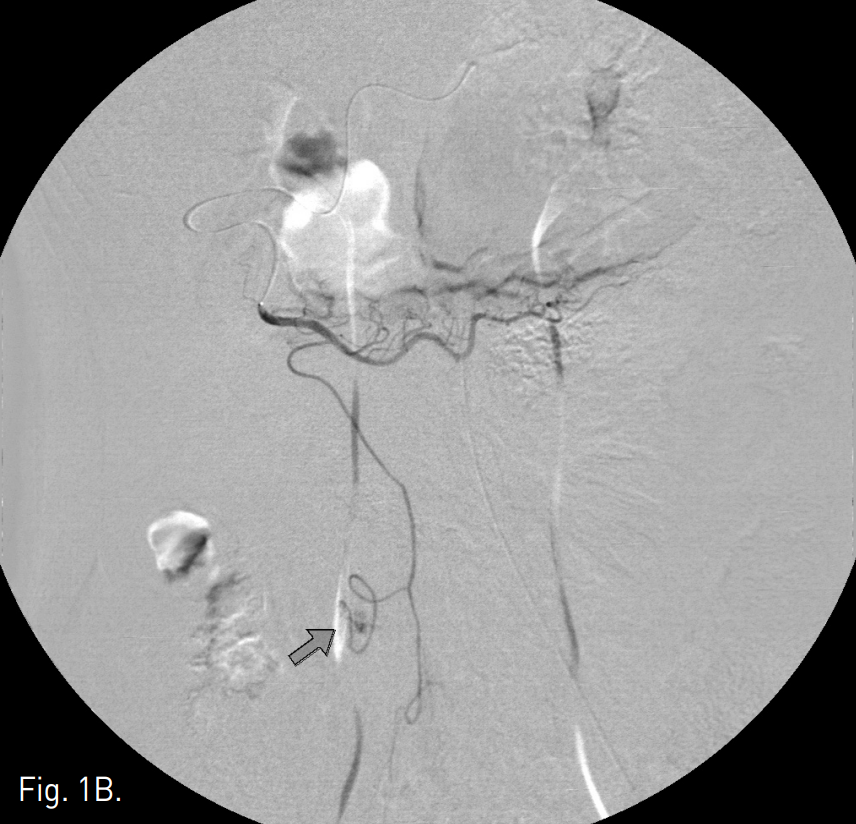

Fig. 1

A, B. Celiac angiogram of delayed phase (A) and selective angiogram of the right gastroepiploic artery (B) show extravasation of contrast media (arrow) from an omental branch of right gastroepiploic artery.